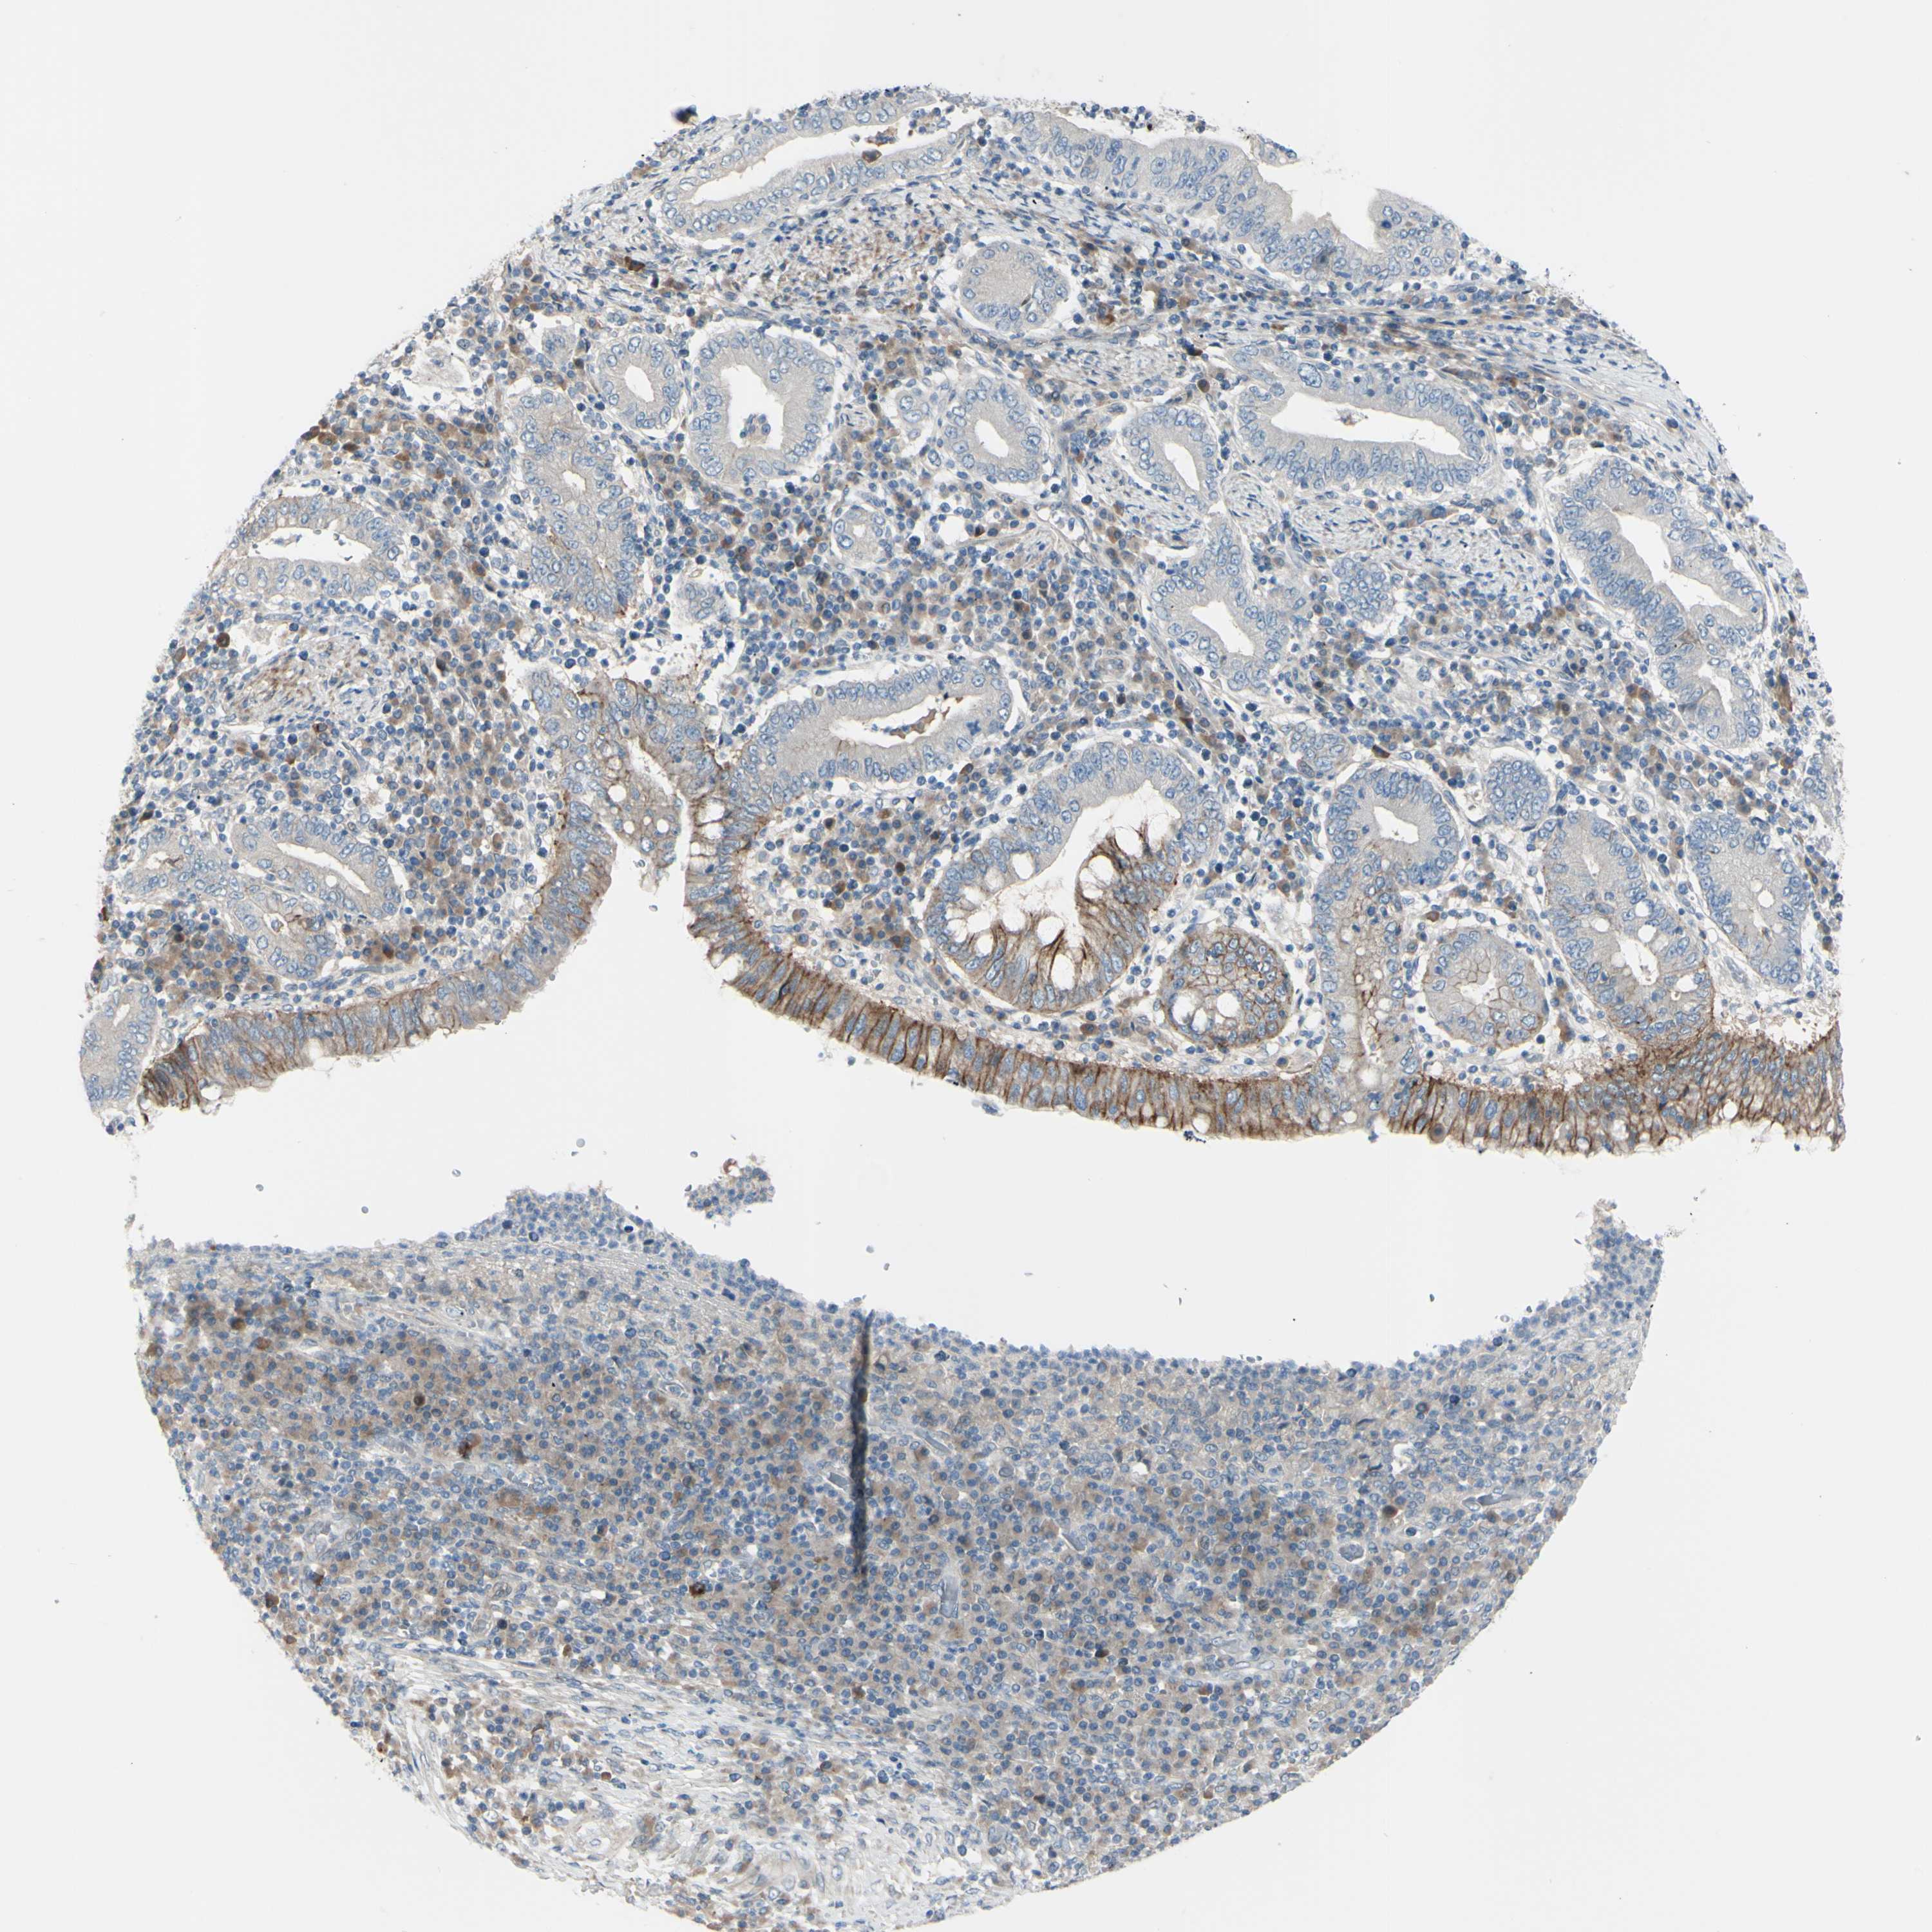

STOMACH CANCER - Protein expressioni

A mouse-over function shows sample information and annotation data. Click on an image to view it in a full screen mode. Samples can be filtered based on level of antibody staining by selecting one or several of the following categories: high, medium, low and not detected. The assay and annotation is described here.

Note that samples used for immunohistochemistry by the Human Protein Atlas do not correspond to samples in the TCGA dataset.

Antibody stainingi

Antibody staining in the annotated cell types in the current human tissue is reported as not detected, low, medium, or high, based on conventional immunohistochemistry profiling in selected tissues. This score is based on the combination of the staining intensity and fraction of stained cells.

Each image is clickable and will lead to virtual microscopy that enables deeper exploration of all samples and also displays staining intensity scores, fraction scores and subcellular localization as well as patient and tissue information for each sample.

Antibody HPA010537

Staining

High

Medium

Low

Not detected

Intensity

Strong

Moderate

Weak

Negative

Quantity

>75%

75%-25%

<25%

None

Location

Nuclear

Cytoplasmic/membranous

Cytoplasmic/membranous,nuclear

Adenocarcinoma, NOS

Adenocarcinoma, High grade